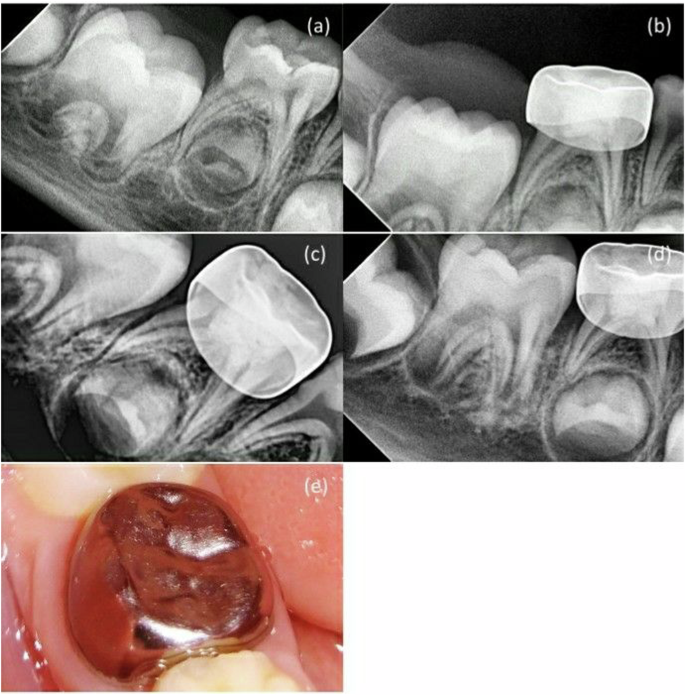

Furthermore, in MTA + NaOCl gel group, a canal obliteration was detected in one case which was not regarded as a radiographic failure. At the 12-month follow-up, the clinical success rate for both groups remained to be 90%, while the radiographic success rate for MTA + NaOCl gel group also remained at 95%. In contrast, MTA + DW group experienced a decrease in radiographic success rate to 85% due to the diagnosis of internal root resorption in two cases (10.0%). Nevertheless, no statistically significant difference was observed in the clinical and radiographic success rates between the two groups at different follow-up intervals (p > 0.05) (Tables 2, 3, 4), suggesting that the MTA + DW group did not outperform the MTA + NaOCl gel group in improving treatment outcomes (Figs. 2, 3, 4).

The results of the current study suggested that at 12-month follow-up, one case exhibited furcal radiolucency and internal and external root resorption in both study groups. However, the MTA + DW group reported three cases with external root resorption and one with abscess. Pathological resorption can also occur in primary teeth when the pulp is infected. The bone destruction associated with pathological resorption causes rapid root loss of the primary tooth, leading to premature tooth loss [44]. This finding contrasts with many studies [45,46,47,48,49], which suggested no external or internal root resorption was detected in the MTA + DW group. However, as reported by Godgi et al. [34], one tooth exhibited internal resorption at a 3-month follow-up, which did not advance to cause further perforation of the root over the subsequent 9 months. Comparable observations were noted in two cases during a period of 25–38 months in a study conducted by Holan et al. [46] and after 12 months in the Jabbarifar et al. [50] study. The result could explained by the fact that the WMTA + NaOCl gel mixture exhibited higher antibacterial efficacy. According to Al Kurdi et al. [39], mixing white Portland cement with 2.2% NaOCl gel enhanced its antibacterial efficacy against E. Faecalis. In addition, according to Karkoutly et al. [7], the WMTA mixed with 2.25% NaOCl gel started with a pH of 9.7 during the initial 24 h and rose to 11.6 after 28 days. Furthermore, the WMTA mixed with DW recorded a pH of 8.5, which also increased to 11.1, demonstrating that both combinations resulted in an alkaline pH. However, the MTA combined with 2.25% NaOCl gel showed greater alkalinity, contributing to its antibacterial efficacy and thereby improving treatment results [7]. Teeth that didn’t respond well to treatment and showed outcome failures were either treated with root canal therapy or extracted.